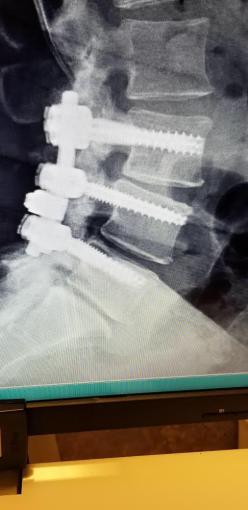

Before we hop into the pictures, I want to share with you that I will be having yet another doggone spine surgery on Wednesday of this week. As some longtime readers may remember, I had 2 such surgeries (in addition to a shoulder surgery!) in 2015 that kept me down and out for quite a long time, then 2 more in 2016. This one, too, will be very difficult (laminectomy, hardware replacement and fusion), but I’m hoping to have a clear enough head to bring you my 2017 Christmas decor along with…drumroll, please…a “Better Kansas City” segment taped right here in our home last Friday!!! I’ve been preparing for it since October (walking with the assistance of a cane and walker slows me down considerably!) and wanted it to be extra special knowing I will not be posting again for quite some time. I do hope you’ll look for that post (if the post-op pains and/or drugs aren’t too overwhelming!) coming sometime before Christmas. My husband will deliver a quick post on how I’m progressing along with a “proof of life” photo. 🙂 The surgery itself is expected to take only 3-4 hours (half the time of that 2nd one in 2015 that was 8 hours long!), and my hospital stay will be 3-4 days. Then it’s home to start getting better for 2018!!!